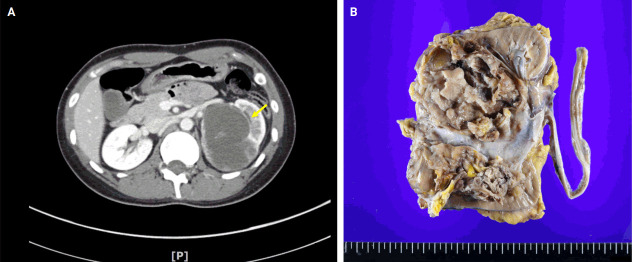

BCOR-rearranged sarcoma was classified by the World Health Organization in 2020 as a new subgroup of undifferentiated small round-cell sarcoma. It is known to occur very rarely in the kidney. This report presents the first case of a primary renal BCOR::CCNB3 sarcoma in a 22-year-old woman. An 8-cm cystic mass was identified in the left kidney by abdominal pelvic computed tomography. Histopathologic examination revealed the mass to be composed of small round to oval or spindle cells with fibrous septa and a delicate vascular network. A BCOR::CCNB3 fusion was detected by next-generation sequencing-based molecular testing. BCOR::CCNB3 sarcoma presents diagnostic difficulties, highlighting the importance of recognizing its histological features. Immunohistochemical markers are helpful for diagnosis, but genetic molecular testing is necessary for accurate diagnosis. These tumors have a very poor and aggressive prognosis, and an optimal therapeutic regimen has not yet been defined. Therefore, further studies are needed.